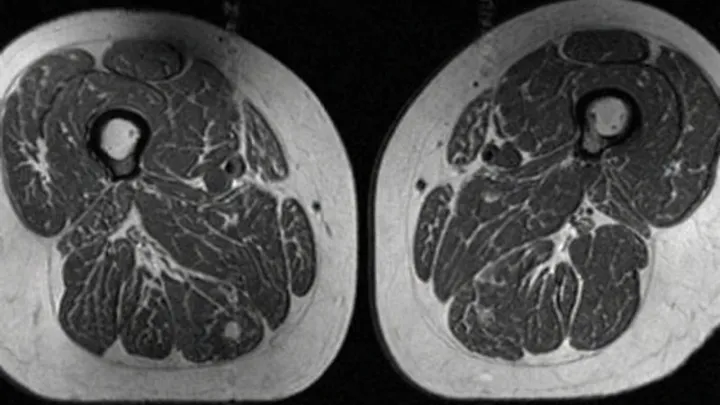

New research links high intake of ultraprocessed foods with increased intermuscular fat, raising concerns for muscle strength, metabolism and long‑term mobility.

A new study links high ultraprocessed food intake to fat streaks in human thigh muscles, reduced muscle quality and potential osteoporosis risk via altered metabolism and inflammation.